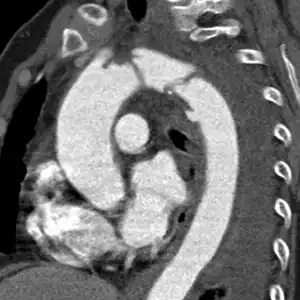

Causes include trauma (either blunt or penetrating) or a complication of an aortic aneurysm (either abdominal or thoracic).[1] Diagnosis is by medical imaging, typically CT scan.[1] It is distinct from aortic dissection, which is a tear through only the inner wall of the aorta.[6]

The condition is often suspected in patients close to death with abdominal trauma or with relevant risk-factors. Diagnosis may be confirmed by ultrasound or CT scan.